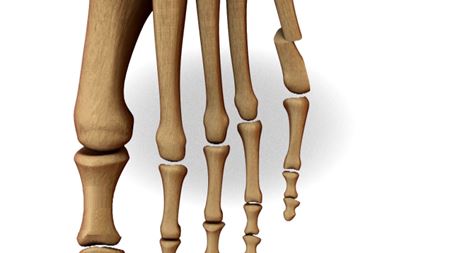

Een bunionette is een pijnlijk uitstekende knobbel net voor de kleine teen.

Die bunionette ontstaat meestal door een lichte scheefstand van het vijfde middenvoetsbeentje en overdruk van te smal schoeisel.